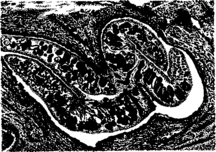

Фасциолез печени. Расширенные желчные протоки с утолщенными стенками

Гистологически в просвете желчных протоков и разветвленной воротной вены можно обнаружить эмболирующих сосуды молодых фасциол, лежащих среди эритроцитов и лейкоцитов, а также разрушение печеночных клеток, гемосидероз, разрастание юных соединительнотканных клеток. При хроническом течении на месте этих повреждений образуются очаги рубцовой ткани. На месте поселения фасциол в желчных ходах развивается вначале катаральный холангит, а затем билиарный цирроз. Печень увеличена, бугристая, плотной консистенции, неравномерно окрашена в зеленовато-коричневый цвет. Снаружи и на разрезе видны толстые (до 2—3 см) извилистые желто-белые тяжи расширенных желчных протоков. Стенки их утолщены (до 3—5 мм), хрящеподобной консистенции, содержат полужидкую зеленовато-коричневую массу с половозрелыми фасциолами, количество которых достигает нескольких десятков и сотен экземпляров. В брюшной полости скопление транссудата. В кишечнике острый катаральный энтерит, каловые массы жидкой консистенции, слабо окрашены желчью. Паренхиматозные органы в состоянии зернистой дистрофии. В подкожной, межмышечной тканях отек, атрофия жировой клетчатки (истощение), желтуха.

Фасциолез. Тела паразитов в просвете небольшого желчного протока